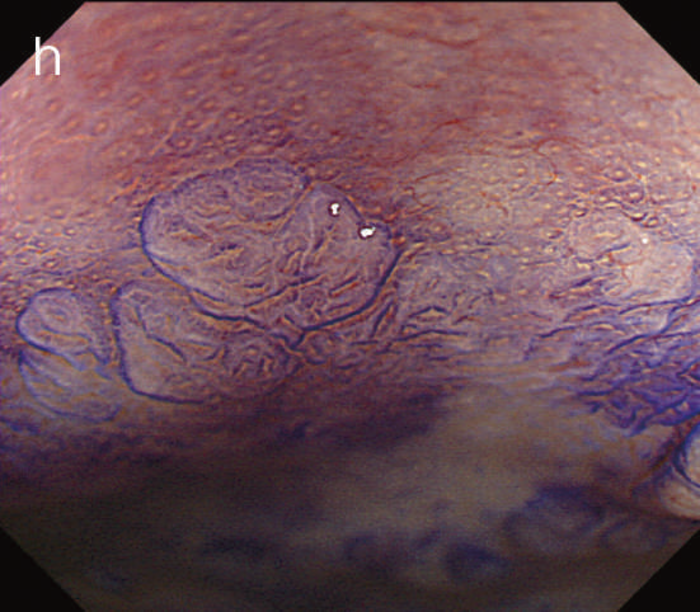

- 白色光像:直腸(下部直腸)に色調変化は乏しく,微小な隆起を複数認めた。背景粘膜は寛解期にあった。

- NBI非拡大像:Brownishな領域が明らかとなった。

- 色素内視鏡像:病変辺縁が明瞭な微小な隆起を複数伴う表面平坦型病変。

- NBI拡大像:口径整でらせん状の微小血管と絨毛状の表面構造を認めた。

- pit pattern像:小型の類円形,管状pitを認めた。